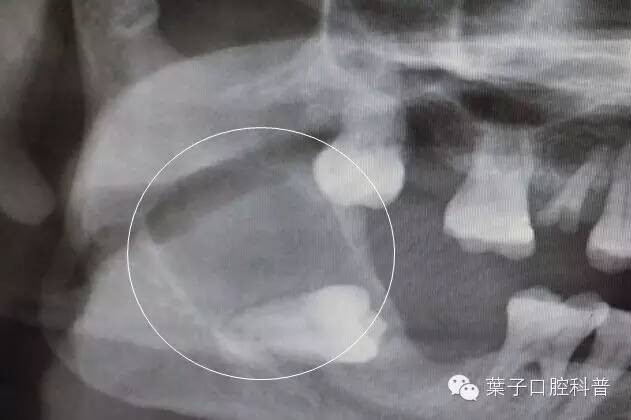

智齿引起下颌骨大面积囊肿

医生特别提醒:如果有需要拔除的智齿,一定是“宜早不宜晚”,也就是趁着年轻赶紧拔除。因为和年纪大的人相比,年轻人智齿的拔除难度小,术后恢复快,并发症少。如果要拔智齿,在18-20岁左右最好。